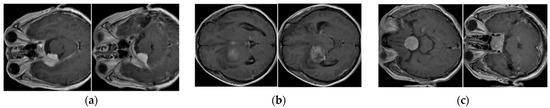

We performed a five-fold cross-validation procedure to evaluate the performance of our proposed method using the BT-Small dataset. For this purpose, we randomly divided the entire BT-Small dataset into five equal parts and assigned them to the training, validation, and testing sets. However, in contrast to the conventional five-fold cross-validation procedure that uses most of the data for training and less data for testing, we used data from one part for training and validation and data from the remaining four parts for the testing dataset, as our study focuses on a small training dataset for the brain tumor image classification system. Among the images in one part that were assigned as the training and validation sets, we randomly selected an equal small number of images in each class for training, and the other images were used for validation. Based on this division, we used the training set to train the classifiers, which were then validated using the validation set. As the FS network mentioned in Section 3.6 requires a support set to evaluate the similarity function between a test image and the images in the support set, we randomly selected a subset of the testing set to form a support set for the FS network. The remaining data of the testing set were assigned to the final test set, which was used to measure the performance of the classifiers on real-world data. The experiments were repeated five times by iterating the training, validation, support and testing set division. Finally, the overall performance of the classification system was measured by taking the average performance of all five experiments. Table 4 summarizes the characteristics of the BT-Small dataset with detailed information on the training, validation, and testing sets. As can be observed from this table, the test dataset is much larger than the training and validation sets. In Figure 7, we show some examples of brain images from the BT-Small dataset.

For the BT-Large dataset, the authors already divided this dataset into training (approximately 80% of the entire dataset) and testing parts (approximately 20% of the entire dataset). Similar to our experiments with the BT-Small dataset, we used a small part of the testing set for training and validation purposes, whereas the remaining part of the dataset was used for testing purposes, as we were dealing with the small training set problem. We repeated our experiments five times, and the final classification performance was measured by taking the average value of the performances obtained in each experiment. Table 5 provides a detailed description of the BT-Large dataset. Figure 8 shows some example images from this dataset.